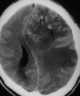

Hurst syndrome

Acute disseminated encephalomyelitis (ADEM), or acute demyelinating encephalomyelitis, is a rare autoimmune disease marked by a sudden, widespread attack of inflammation in the brain and spinal cord. As well as causing the brain and spinal cord to become inflamed, ADEM also attacks the nerves of the central nervous system and damages their myelin insulation, which, as a result, destroys the white matter. [Source: Wikipedia ]